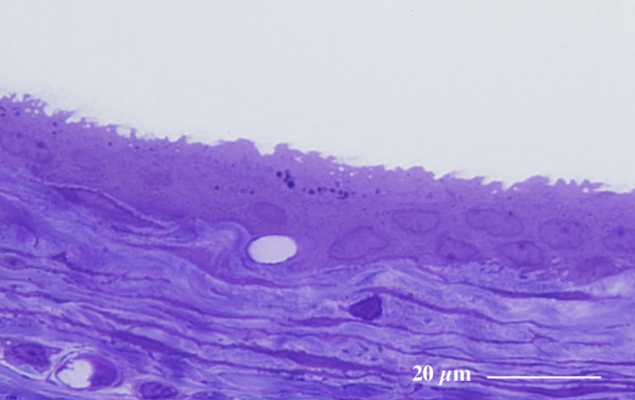

膀 胱(ラット) Urinary bladder ( rat )

厚さ1 µm エポン樹脂準超薄切片のトルイジンブルー染色光学顕微鏡画像

Light microscopic image of 1 µm-semithin epoxy resin section with toluidin-blue staining

膀胱の粘膜は尿を貯留に対応して伸縮しやすい移行上皮によって構成される。

(エポン樹脂包埋準超薄切片のトルイジンブルー染色光顕像)